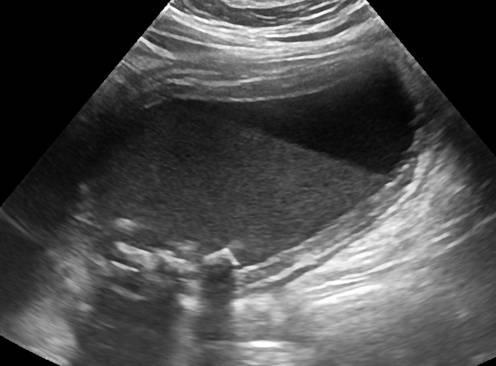

Patient has been fed intravenously for 3 days.

Sludge

highly concentrated bile

Gravity dependent